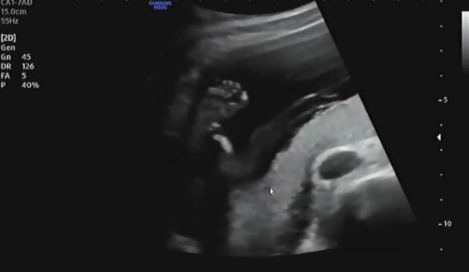

침대에 누워 복부초음파를 보는데 먼저 자궁경부 길이 등을 확인하고 양수량이 적당히 있는지 확인을 했다. 다행히 나는 자궁경부 길이가 4.22cm고 양수량도 적당히 있어서 조산위험이 없다고 했다. 자궁경부 길이가 짧을수록 조산위험이 크기 때문에 절대 안정이 필요하다.